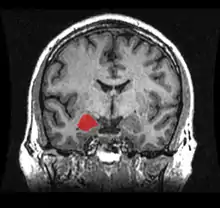

![]() Location of the amygdalae in the human brain | |

The amygdala (/əˈmɪɡdələ/; pl.: amygdalae /əˈmɪɡdəli, -laɪ/ or amygdalas; also corpus amygdaloideum; Latin from Greek, ἀμυγδαλή, amygdalē, 'almond', 'tonsil'[1]) is one of two almond-shaped clusters of nuclei located deep and medially within the temporal lobes of the brain's cerebrum in complex vertebrates, including humans.[2] Shown to perform a primary role in the processing of memory, decision making, and emotional responses (including fear, anxiety, and aggression), the amygdalae are considered part of the limbic system.[3] The term "amygdala" was first introduced by Karl Friedrich Burdach in 1822.[4]